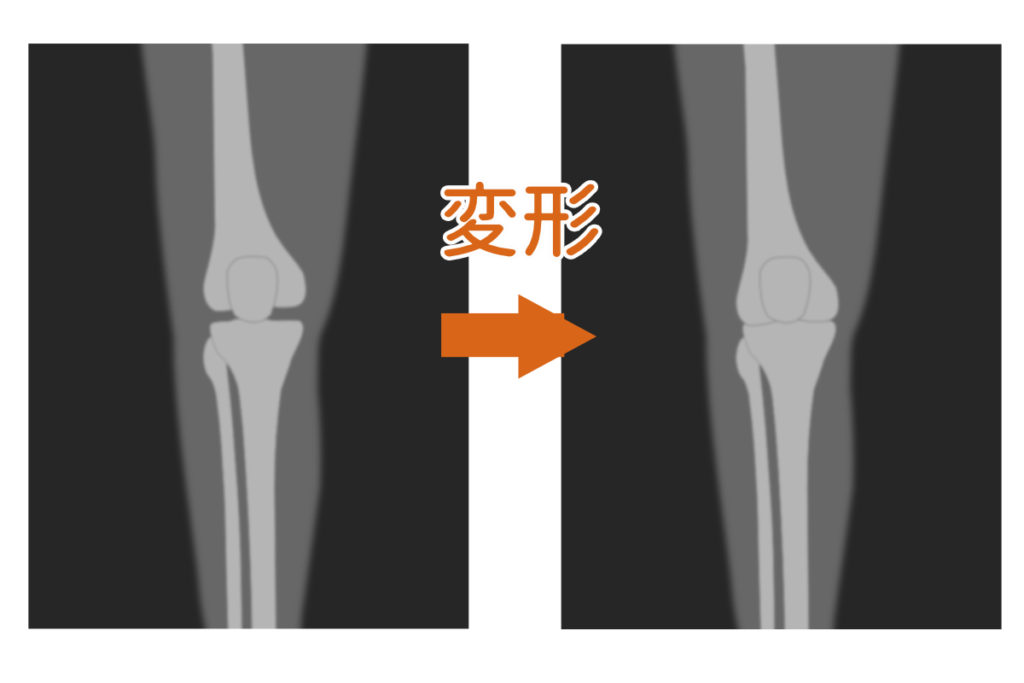

原因は骨だけではない?

膝の痛みのおもな原因

- 運動不足による筋力低下

- 膝の骨の変形

- 膝周辺の筋肉への負担

「膝の骨の変形」は痛みに対する1つの原因になりますが、実際には

”骨の変形により、筋肉や靭帯に負担が大きくなり痛みを感じている”

ようなケースも。

視点を変えれば、

”筋肉が本来の状態にもどれば、改善する可能性がある”

ともいえます。

膝の痛みは筋肉や靭帯への

負担が大きくなることで発生

骨が変形すると……

▼

筋肉・靭帯の負担が増えるため

膝の痛みが出やすい

▼

視点を変えると……

筋肉の状態を取りもどせば

痛みが出にくくなるかも?